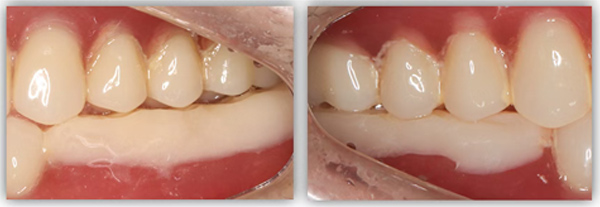

這位患者不到60歲,但由于后牙全部缺失多年,殘留的前牙已松動且上下無法接觸,他基本沒辦法正常咀嚼,人非常消瘦。完成治療后我跟蹤了這個病例一年,從前后對比照片可以看出,能正常吃東西后他的臉上漸漸也有肉了。